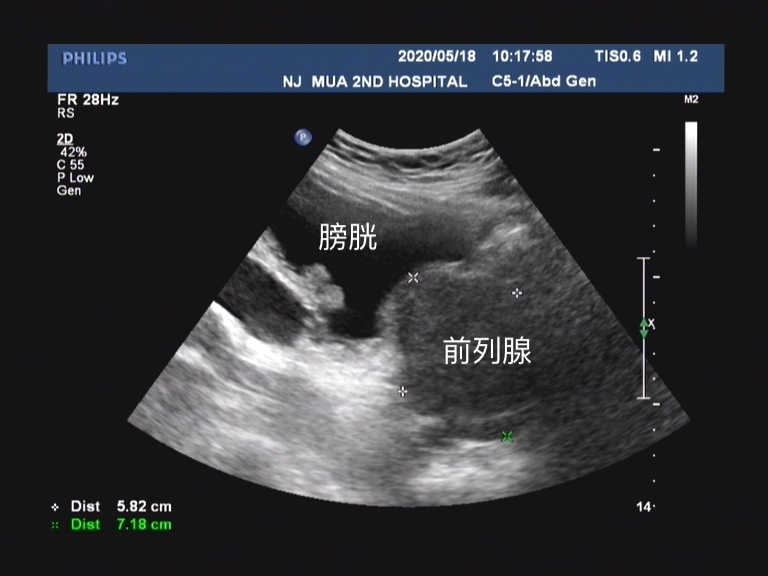

可能讲起来比较难以理解, 我们男性的排尿是当膀胱内充满尿液后会有排尿的冲动信号由膀胱传递至大脑,然后大脑在可以排尿的情况下将信号在传递至膀胱和尿道。这个时候膀胱开始收缩,尿道打开,小便就可以自然排出。而前列腺增生后会带来几种情况,它会刺激我们的膀胱,即使在尿量不充盈的时候也会刺激患者要去排尿,这个时候患者表现出来的就是尿频尿急和夜尿增多,甚至出现尿*禁失**。由于尿道是从前列腺内穿行而出,增生的前列腺腺体又会对尿道产生压迫,这时候就会导致患者的排尿困难。